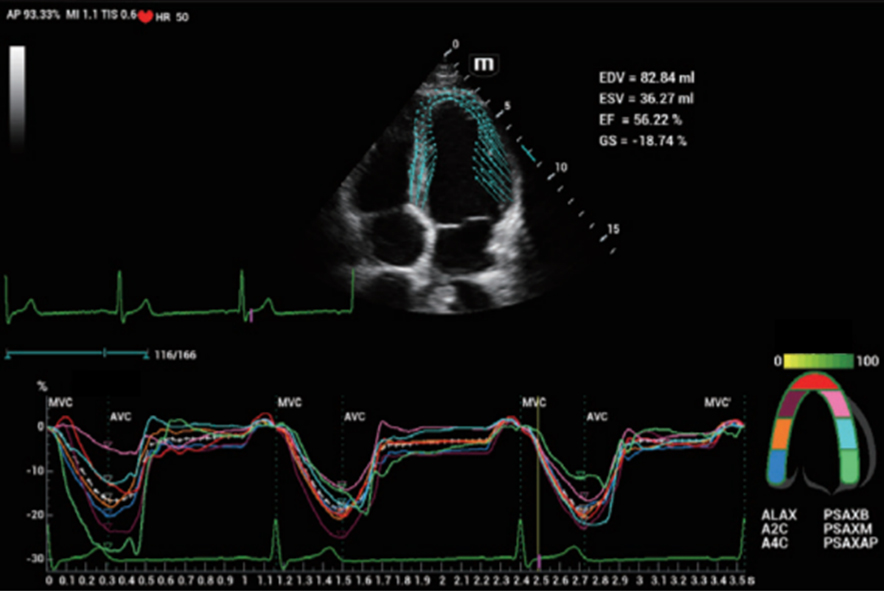

–‰–Ϋ–Ϋ–Ψ–≤–Α―Ü–Η–Ψ–Ϋ–Ϋ–Α―è –Ψ―Ü–Β–Ϋ–Κ–Α –Ε–Β―¹―²–Κ–Ψ―¹―²–Η: HiFR STE

–£ 10 ―Ä–Α–Ζ –±–Ψ–Μ–Β–Β –≤―΄―¹–Ψ–Κ–Α―è ―΅–Α―¹―²–Ψ―²–Α –Κ–Α–¥―Ä–Ψ–≤ –Ω―Ä–Η ―Ä–Α–±–Ψ―²–Β ―Ä–Β–Ε–Η–Φ–Α STE

–£―΄―¹–Ψ–Κ–Α―è ―΅―É–≤―¹―²–≤–Η―²–Β–Μ―¨–Ϋ–Ψ―¹―²―¨ –Κ –¥–≤–Η–Ε–Β–Ϋ–Η―é –¥–Μ―è –Ω–Ψ–≤―΄―à–Β–Ϋ–Η―è ―¹―²–Α–±–Η–Μ―¨–Ϋ–Ψ―¹―²–Η –Η ―²–Ψ―΅–Ϋ–Ψ―¹―²–Η

HiFR STE –Ϋ–Ψ–≤–Ψ–Ψ–±―Ä–Α–Ζ–Ψ–≤–Α–Ϋ–Η―è –Φ–Ψ–Μ–Ψ―΅–Ϋ–Ψ–Ι –Ε–Β–Μ–Β–Ζ―΄

HiFR STE –Ω–Β―΅–Β–Ϋ–Η

–‰–Ϋ–Ϋ–Ψ–≤–Α―Ü–Η–Ψ–Ϋ–Ϋ–Α―è –Ψ―Ü–Β–Ϋ–Κ–Α –Ε–Β―¹―²–Κ–Ψ―¹―²–Η: HiFR STE

–£ 10 ―Ä–Α–Ζ –±–Ψ–Μ–Β–Β –≤―΄―¹–Ψ–Κ–Α―è ―΅–Α―¹―²–Ψ―²–Α –Κ–Α–¥―Ä–Ψ–≤ –Ω―Ä–Η ―Ä–Α–±–Ψ―²–Β ―Ä–Β–Ε–Η–Φ–Α STE

–£―΄―¹–Ψ–Κ–Α―è ―΅―É–≤―¹―²–≤–Η―²–Β–Μ―¨–Ϋ–Ψ―¹―²―¨ –Κ –¥–≤–Η–Ε–Β–Ϋ–Η―é –¥–Μ―è –Ω–Ψ–≤―΄―à–Β–Ϋ–Η―è ―¹―²–Α–±–Η–Μ―¨–Ϋ–Ψ―¹―²–Η –Η ―²–Ψ―΅–Ϋ–Ψ―¹―²–Η

HiFR STE –Ϋ–Ψ–≤–Ψ–Ψ–±―Ä–Α–Ζ–Ψ–≤–Α–Ϋ–Η―è –Φ–Ψ–Μ–Ψ―΅–Ϋ–Ψ–Ι –Ε–Β–Μ–Β–Ζ―΄

HiFR STE –Ω–Β―΅–Β–Ϋ–Η